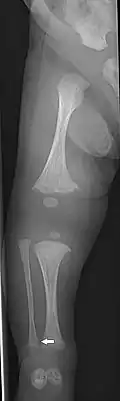

Having the same clinical features as Type IV, it is distinguished histologically by "mesh-like" bone appearance. Further characterized by the "V triad" consisting of (a) radio-opaque band adjacent to growth plates, (b) hypertrophic calluses at fracture sites, and (c) calcification of the radio-ulnar interosseous membrane.[24]

OI Type V leads to calcification of the membrane between the two forearm bones, making it difficult to turn the wrist. Another symptom is abnormally large amounts of repair tissue (hyperplasic callus) at the site of fractures. Other features of this condition include radial head dislocation, long bone bowing, and mixed hearing loss.

OI Type V in an adult